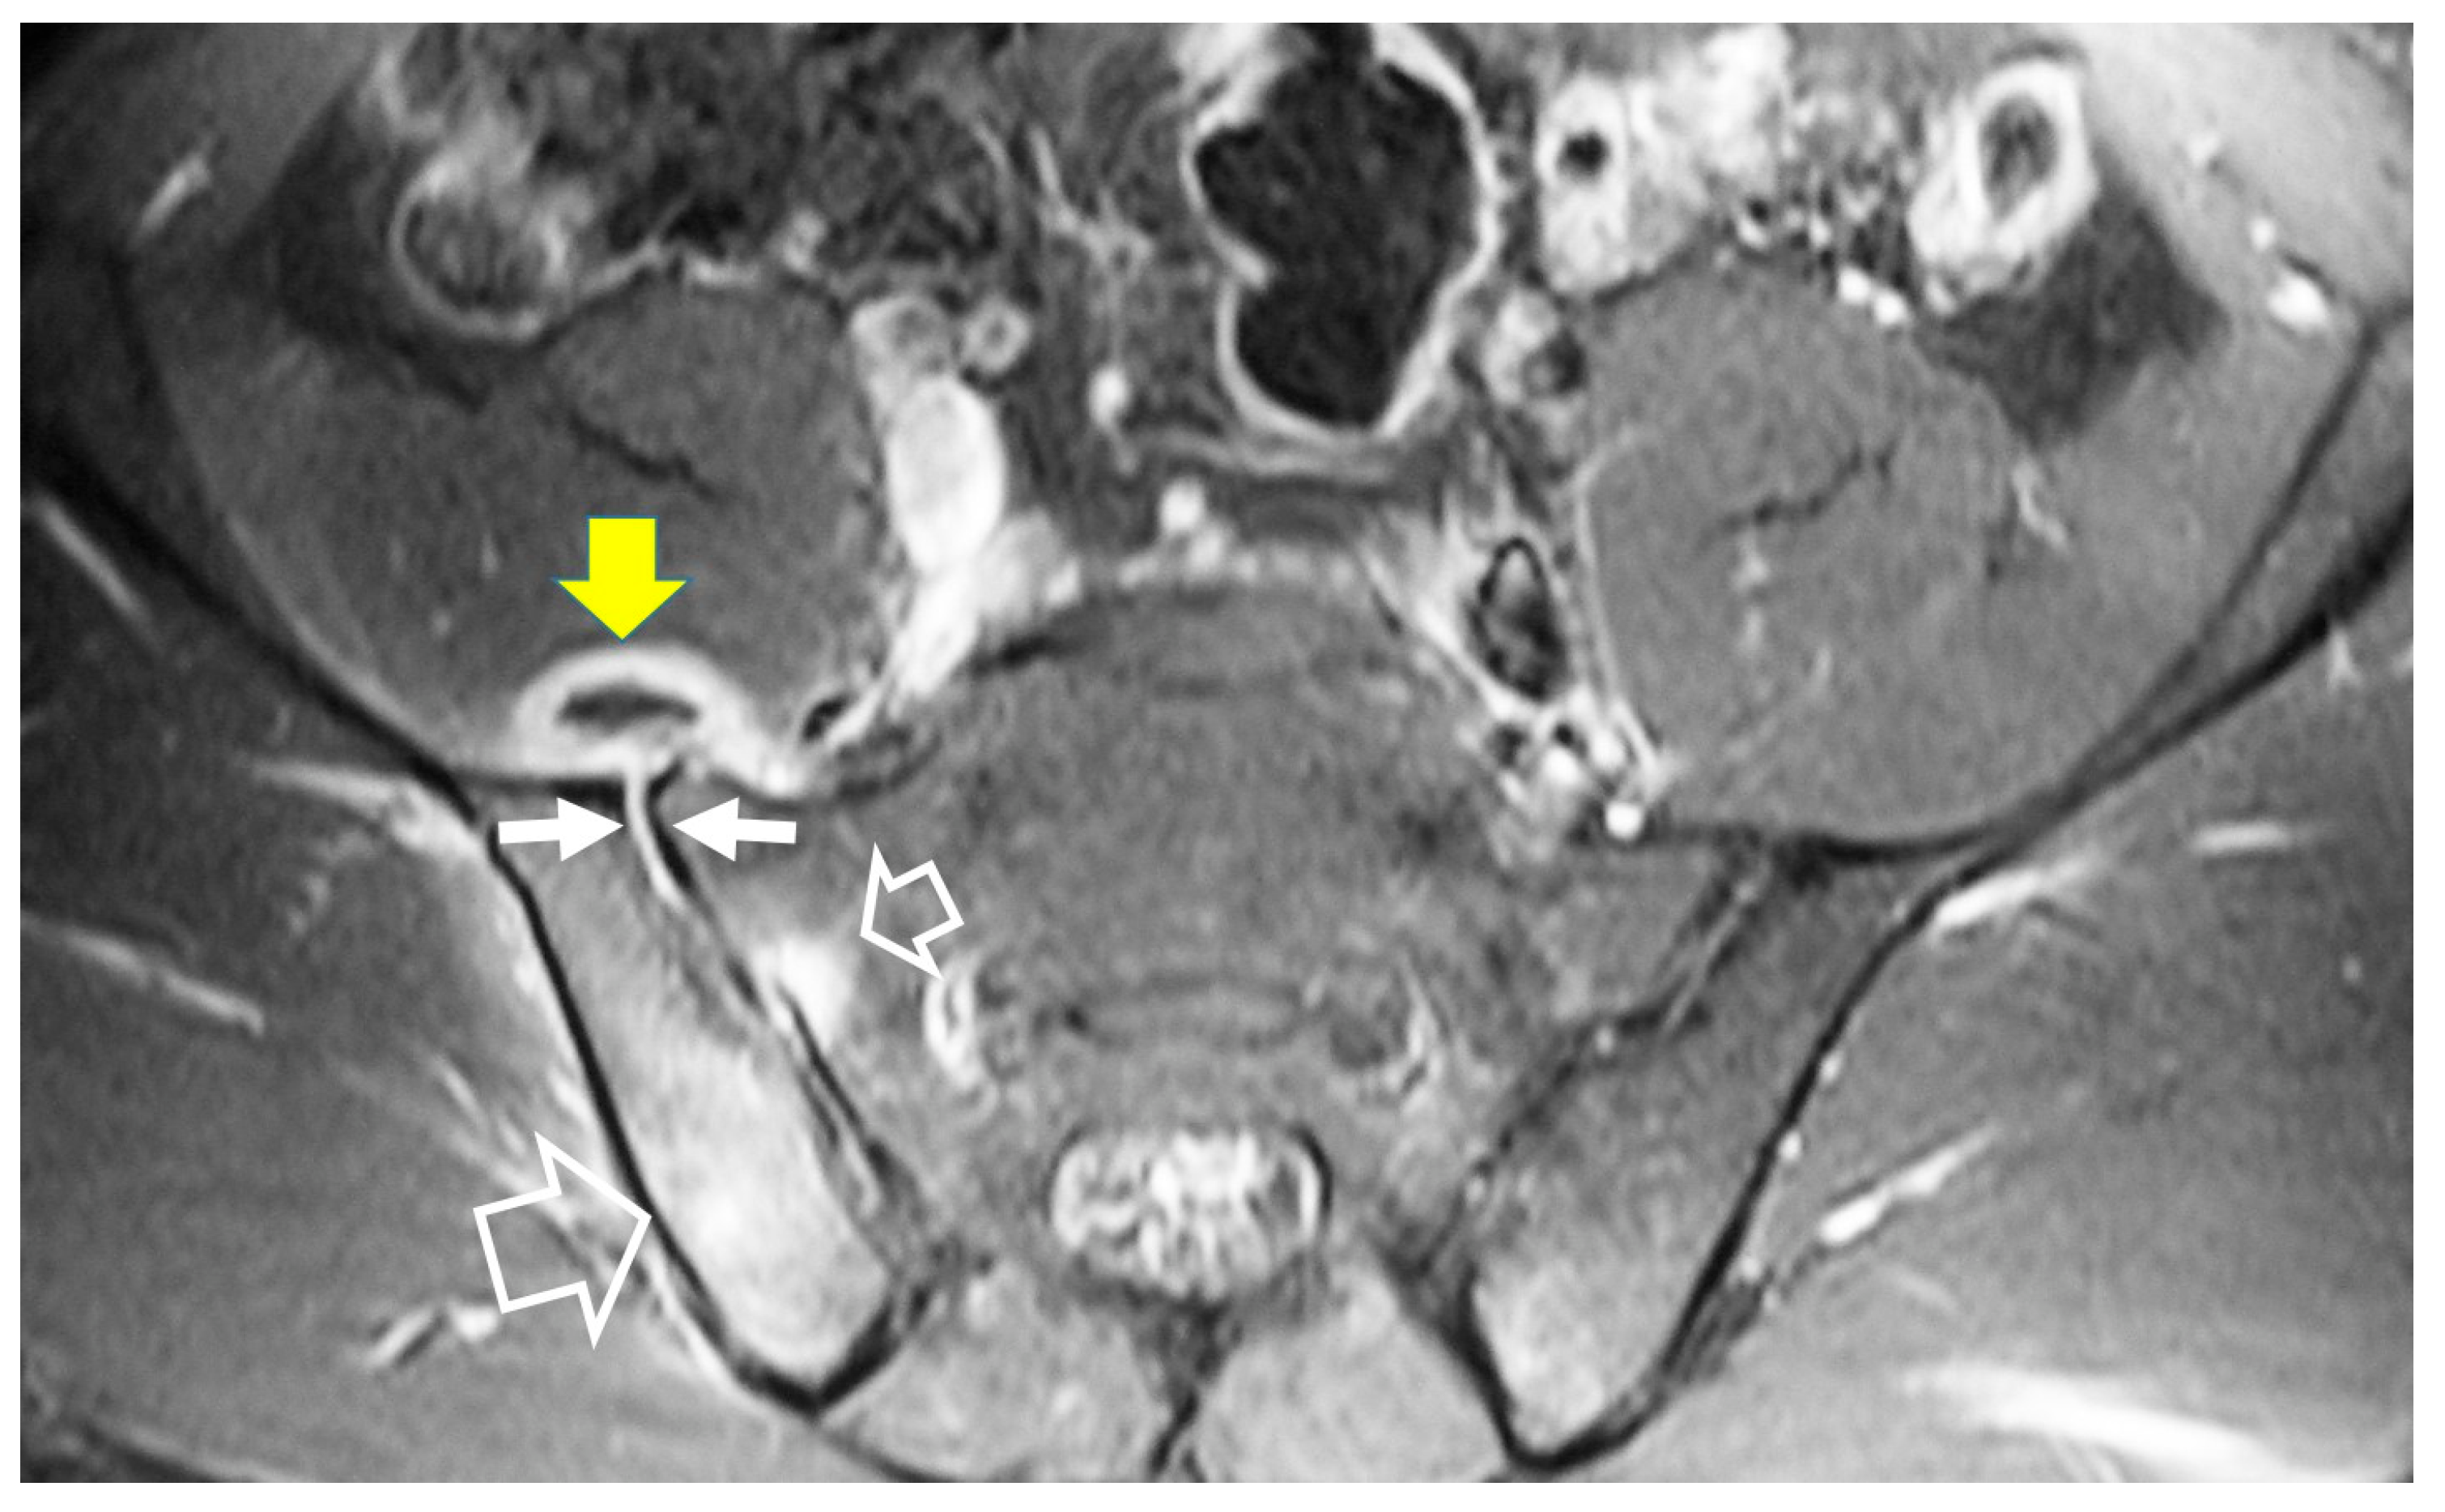

- Bozgeyik, Z.; Ozdemir, H.; Demirdag, K.; Ozden, M.; Sonmezgoz, F.; Ozgocmen, S. Clinical and MRI findings of brucellar spondylodiscitis. Eur. J. Radiol. 2008, 67, 153–158. [Google Scholar] [CrossRef]

- Bozgeyik, Z.; Aglamis, S.; Bozdag, P.G.; Denk, A. Magnetic resonance imaging findings of musculoskeletal brucellosis. Clin. Imaging 2014, 38, 719–723. [Google Scholar] [CrossRef]

- Ozaksoy, D.; Yucesoy, K.; Yucesoy, M.; Kovanlikaya, I.; Yuce, A.; Naderi, S. Brucellar spondylitis: MRI findings. Eur. Spine J. 2001, 10, 529–533. [Google Scholar] [CrossRef] [PubMed]

- Harman, M.; Unal, O.; Onbasi, K.T.; Kiymaz, N.; Arslan, H. Brucellar spondylodiscitis: MRI diagnosis. Clin. Imaging 2001, 25, 421–427. [Google Scholar] [CrossRef] [PubMed]

- Chelli Bouaziz, M.; Ladeb, M.F.; Chakroun, M.; Chaabane, S. Spinal brucellosis: A review. Skelet. Radiol. 2008, 37, 785–790. [Google Scholar] [CrossRef]

- al-Shahed, M.S.; Sharif, H.S.; Haddad, M.C.; Aabed, M.Y.; Sammak, B.M.; Mutairi, M.A. Imaging features of musculoskeletal brucellosis. Radiographics 1994, 14, 333–348. [Google Scholar] [CrossRef]

- Guo, H.; Lan, S.; He, Y.; Tiheiran, M.; Liu, W. Differentiating brucella spondylitis from tuberculous spondylitis by the conventional MRI and MR T2 mapping: A prospective study. Eur. J. Med. Res. 2021, 26, 125. [Google Scholar] [CrossRef]

- Li, W.; Zhao, Y.H.; Liu, J.; Duan, Y.W.; Gao, M.; Lu, Y.T.; Yao, L.; Li, S.L. Imaging diagnosis of brucella spondylitis and tuberculous spondylitis. Zhonghua Yi Xue Za Zhi 2018, 98, 2341–2345. [Google Scholar] [CrossRef]